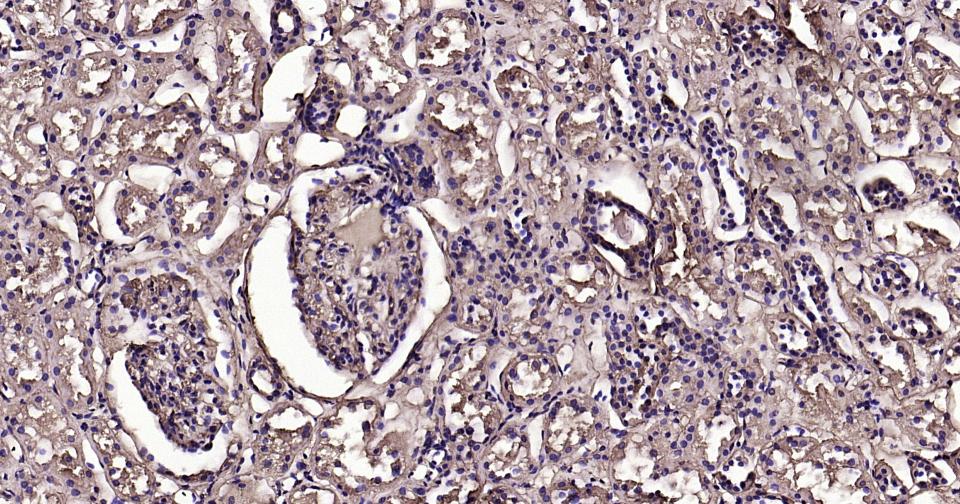

Paraformaldehyde-fixed, paraffin embedded Human Kidney; Antigen retrieval by boiling in sodium citrate buffer (pH6.0) for 15 min; Antibody incubation with Calmodulin 1 Monoclonal Antibody, Unconjugated(bsm-61141R) at 1:200 overnight at 4°C, followed by conjugation to the SP Kit (Rabbit, SP-0023)and DAB (C-0010) staining.